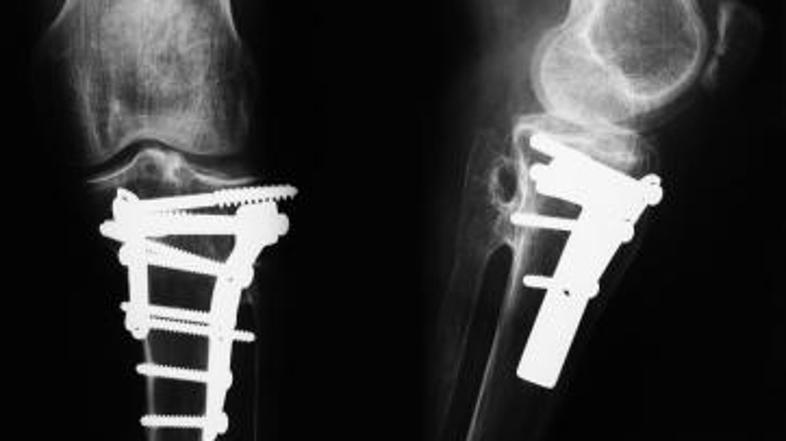

Sedemdesetletni Roy Calloway si je daljnega leta 1958 v nesreči z motorjem desno nogo zlomil na več mestih. Šest mesecev je preživel na invalidskem vozičku, dve leti pa si je pri hoji pomagal z berglami. Po vsem tem času pa je še vedno čutil bolečino, vendar so ga zdravniki pomirili, da je to le posledica zdravljenja.

Z leti pa je bila bolečina vedno hujša. Pred kratkim se je tako odločil, da gre znova v bolnišnico. Rentgenska slika je presenetljivo pokazala, da se tri kosti niso pravilno zarasle.